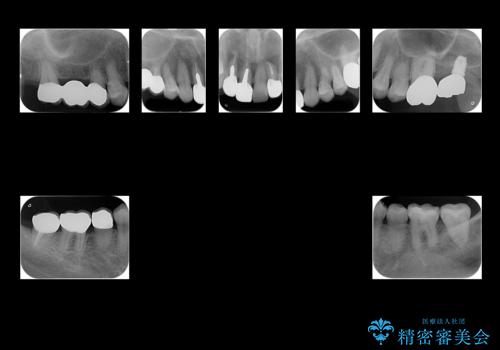

左上は他院でインプラントを入れたが、クラウンの脱離を繰り返して、仮歯に戻したあともうそれでいいと言われたとのことでした。

仮歯はすっかり劣化、変質しており、上記の写真のように隣の歯が虫歯になっている状態でした。

インプラントの製造会社は当院で使っているものと異なったため、ドライバー等購入し対応しました。

全体的にプラスチックで治療してあり、劣化していたのと、また、右上6番は根の治療がされていましたがプラスチックで埋めてあるだけで中を見たところ残念ながら割れていました。その歯は抜歯し⑤6⑦ブリッジにしています。